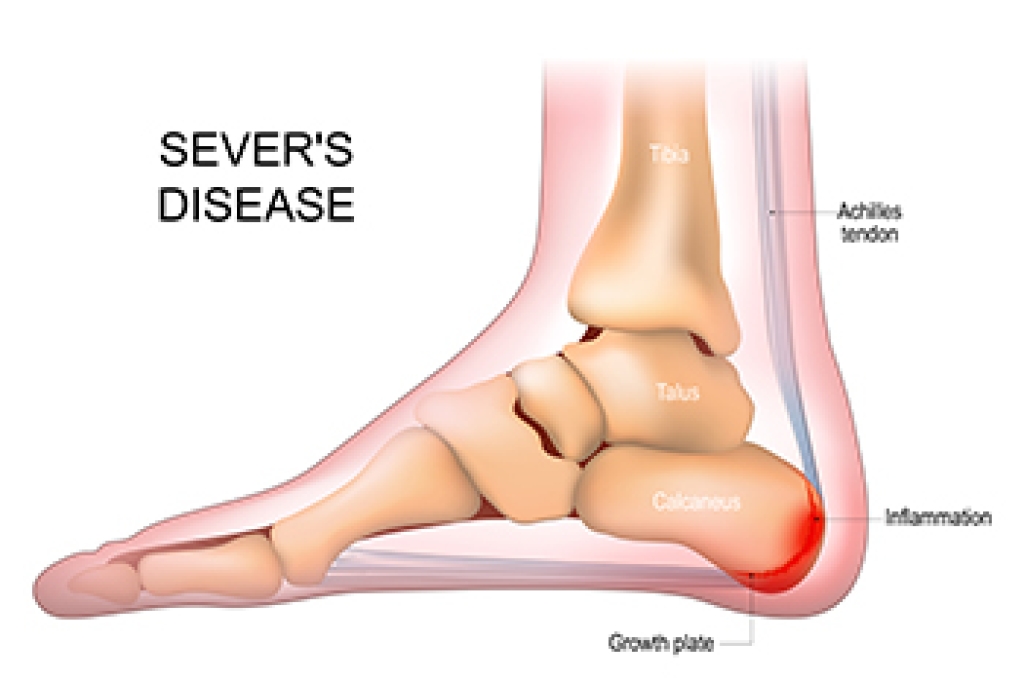

Understanding Sever’s Disease

Sever’s disease is a common cause of heel pain in growing children, particularly those who are active in sports. It occurs when the growth plate in the heel becomes inflamed due to repetitive stress and tension from the Achilles tendon. This condition is most common during periods of rapid growth, when bones lengthen faster than muscles and tendons can adapt. Causes include excessive running, jumping, and footwear that lacks adequate support. Symptoms include pain and tenderness at the back of the heel, swelling, and difficulty walking or participating in physical activities. The discomfort may worsen with activity and improve with rest. If your active child has heel pain, it is suggested that you consult a podiatrist who can accurately diagnose and manage Sever’s disease.

Sever’s Disease

Sever’s disease is also known as calcaneal apophysitis, which is a medical condition that causes heel pain I none or both feet. The disease is known to affect children between the ages of 8 and 14.

Sever’s disease occurs when part of the child’s heel known as the growth plate (calcaneal epiphysis) is attached to the Achilles tendon. This area can suffer injury when the muscles and tendons of the growing foot do not keep pace with bone growth. Therefore, the constant pain which one experiences at the back of the heel will make the child unable to put any weight on the heel. The child is then forced to walk on their toes.

Symptoms

Acute pain – Pain associated with Sever’s disease is usually felt in the heel when the child engages in physical activity such as walking, jumping and or running.

Highly active – Children who are very active are among the most susceptible in experiencing Sever’s disease, because of the stress and tension placed on their feet.